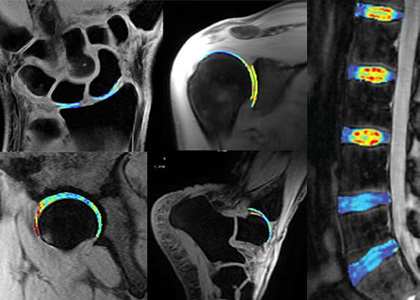

Musculoskeletal Research Center

Cleveland Clinic's Musculoskeletal Research Center (MSRC) brings together researchers across the spectrum of biomedical discovery—translational scientists and engineers, orthopaedic surgeons, radiologists and imaging scientists, rheumatologists, physiatrists, pathologists, neuroscientists, and biostatisticians—to discover, translate and innovate to improve patient care.

Multidisciplinary investigators in Cleveland Clinic’s Musculoskeletal Research Center study various topics including orthopaedics, rheumatology, spine, physiatry, imaging, pathology, neurosciences and biostatistics.